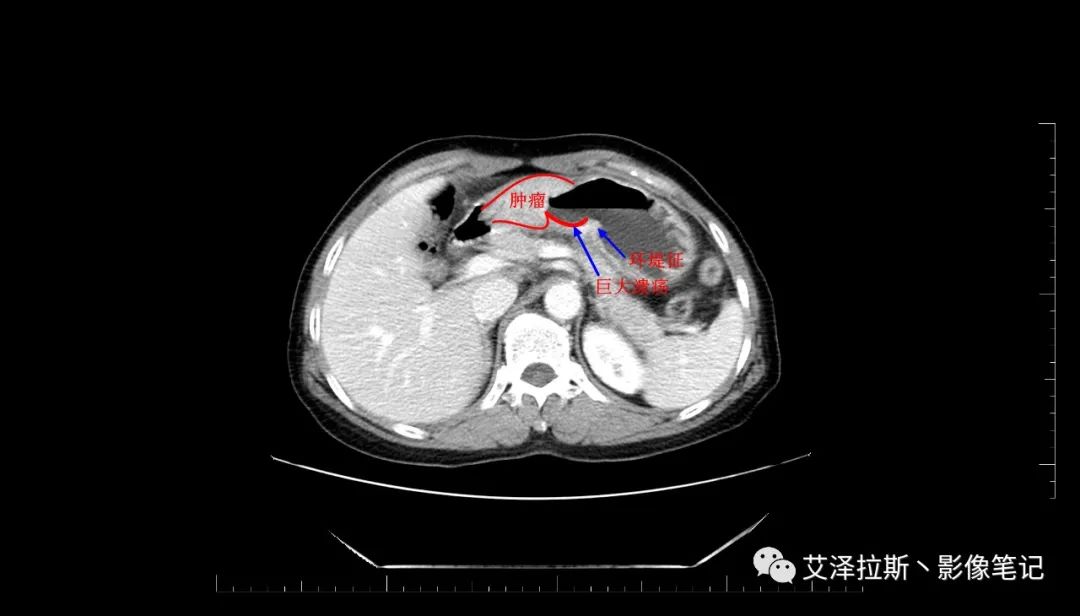

圖2 腫瘤

【影像所見】 胃竇部狹窄,胃壁環(huán)形增厚,小彎側(cè)見一巨大潰瘍,周圍伴“環(huán)堤征”,漿膜面不完整,胃周脂肪見網(wǎng)格狀條索影,病灶與肝臟左葉、胰腺鉤突脂肪間隙消失,增強(qiáng)掃描病灶明顯強(qiáng)化。引流區(qū)內(nèi)約15個區(qū)域淋巴結(jié)受累。

【診斷意見】 胃竇部胃癌(T4N3期) 該病例腫塊突破漿膜層,與肝臟左葉、胰腺鉤突分界不清,脂肪界面消失,定為T4期; 受累及的淋巴結(jié)為15個區(qū)域,定為N3; 有無遠(yuǎn)處轉(zhuǎn)移尚不明確,所以M期暫時無法確定。